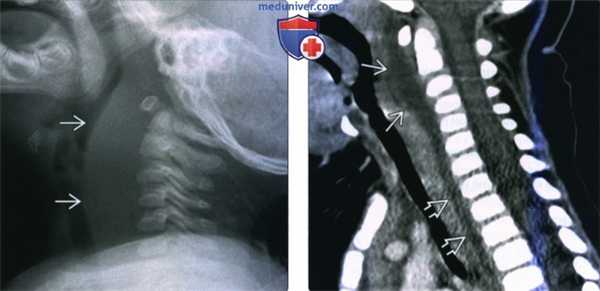

(Слева) Рентгенограмма в боковой проекции, 12-месячный ребенок с сепсисом. Отмечается значительное утолщение предпозвоночных мягких тканей.

(Справа) КТ с КУ, сагиттальная реконструкция, этот же пациент. Четко выявлена причина утолщения предпозвоночных тканей - крупный заглоточный абсцесс с выпуклой передней поверхностью. Жидкостное содержимое распространяется в заднее средостение.

2. Рентгенография при заглоточном абсцессе:

• Рентгенография:

о Рентгенограмма в боковой проекции:

- У детей: необходимо выполнять на вдохе и с разогнутой шеей:

У маленьких детей сгибание шеи может привести к ложному расширению предпозвоночных тканей

Рентгеноскопия в боковой проекции: позволяет отличить истинное расширение от ложного

- Информативность исследования невелика, поскольку оно не позволяет оценить распространенность процесса и четко дифференцировать целлюлит/флегмону от абсцесса

о Расширение предпозвоночных тканей

о В редких случаях в ЗГП обнаруживается воздух, что, при отсутствии сведений о травме глотки, говорит в пользу абсцесса

о Нормальная толщина предпозвоночных тканей

- С2: ≤ 7 мм в любом возрасте

- С6: ≤ 14 мм у детей младше 15 лет, < 22 мм у взрослых

(Слева) Рентгенограмма в боковой проекции, ребенок трех лет, шея находится в нейтральном положении. Определяется выбухание предпозвоночных мягких тканей. Как можно понять по куполу легкого, снимок сделан на выдохе.

(Справа) Этот же ребенок, рентгеноскопия в боковой проекции. Снимок сделан во время глубокого вдоха. Видно, что толщина предпозвоночных тканей в норме.